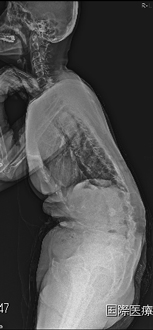

腰が曲がって前に重心があるため前かがみになってしまいます。

前と左に曲がって立位困難です。